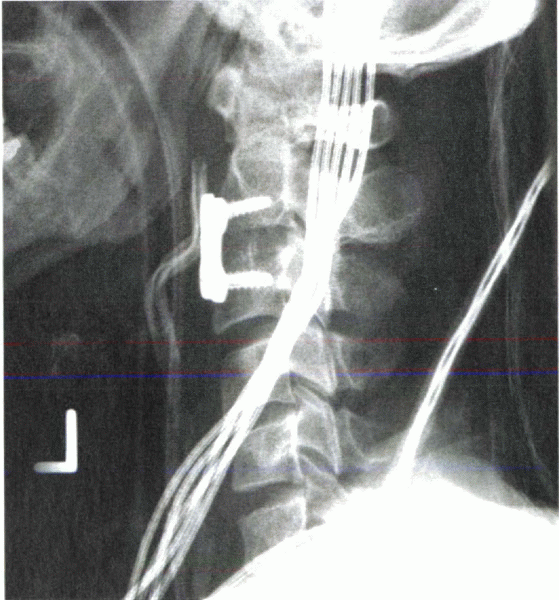

![]() |

|

Figure 28-11 Lateral mass screws can provide rigid fixation to the subaxial spine. (A) Note the lateral angulation of the screws on the anteroposterior view. (B) On the lateral view, the screws approximate the plane of the facet joints.

placed through the plate. The disadvantage is that the location and

orientation of the screw are determined by the distance between the

holes in the plate. The advantage of screw-rod constructs is that the

screws can be placed at each level first, allowing placement to be

determined by the patient’s anatomy. The screws are connected rigidly

to a rod (Fig. 28-11). Rod contouring can be challenging.

been advocated, with plate and rod techniques available today. To

orient the screw head as flush to the plate as possible, the initial

technique, popularized by Roy-Camille, placed the screw perpendicular

to the longitudinal axis, angled laterally about 10 degrees. In efforts

to stay farther away from the vertebral artery (transverse foramen), An

recommended starting the screw more inferior and medial, angling it

cranially about 15 degrees and laterally about 30 degrees. To place a

longer screw in more bone, Magerl advocated aligning the screw parallel

with the facet joint, angling it laterally by 25 degrees.